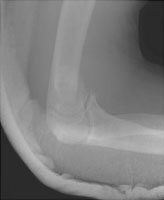

- Click on the image for a larger versionALateral radiograph of the elbow.